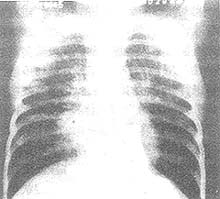

其他輔助檢查:胸部X線徵象呈兩肺瀰漫性結節浸潤或網織狀陰影,病灶可融合呈廣泛浸潤灶影,常分布於肺門或肺底部。可出現兩側胸腔積液徵象。病變較輕者多於1~2周內吸收,亦有延長至數月始吸收者,最後可能遺留散在的鈣化灶。電鏡檢查取新鮮皰疹內液體作電鏡檢查,見皰疹病毒顆粒,或取皰疹內液體接種人胚羊膜組織作病毒分離可確診。